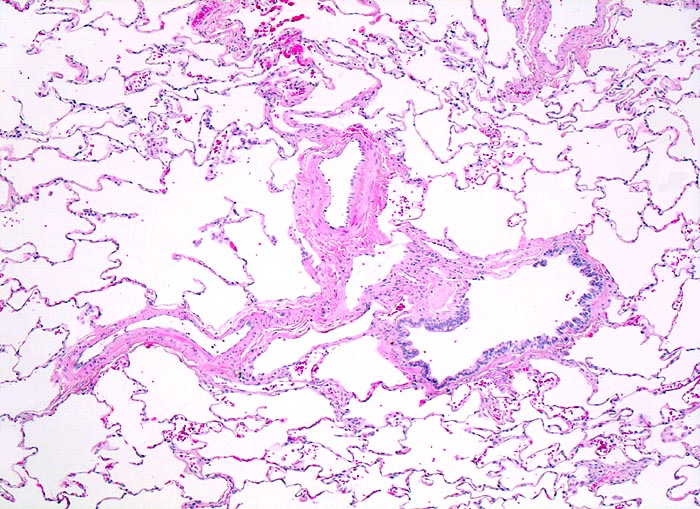

PathoPic ID 4363 - normales Lungenparenchym

normales Lungenparenchym

Normalbefund

Lunge

Lunge, Mediastinum mit Thymus

Die Alveolarsepten sind sehr schlank. Die

Lungenarterienäste verlaufen zusammen mit den Luftwegen. Im Bild ein

Bronchiolus.

Histologie

50

24

männlich